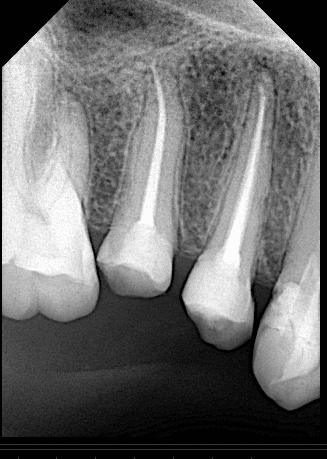

Initial situation showing large carious lesion in the upper premolars

Pre-operative x ray